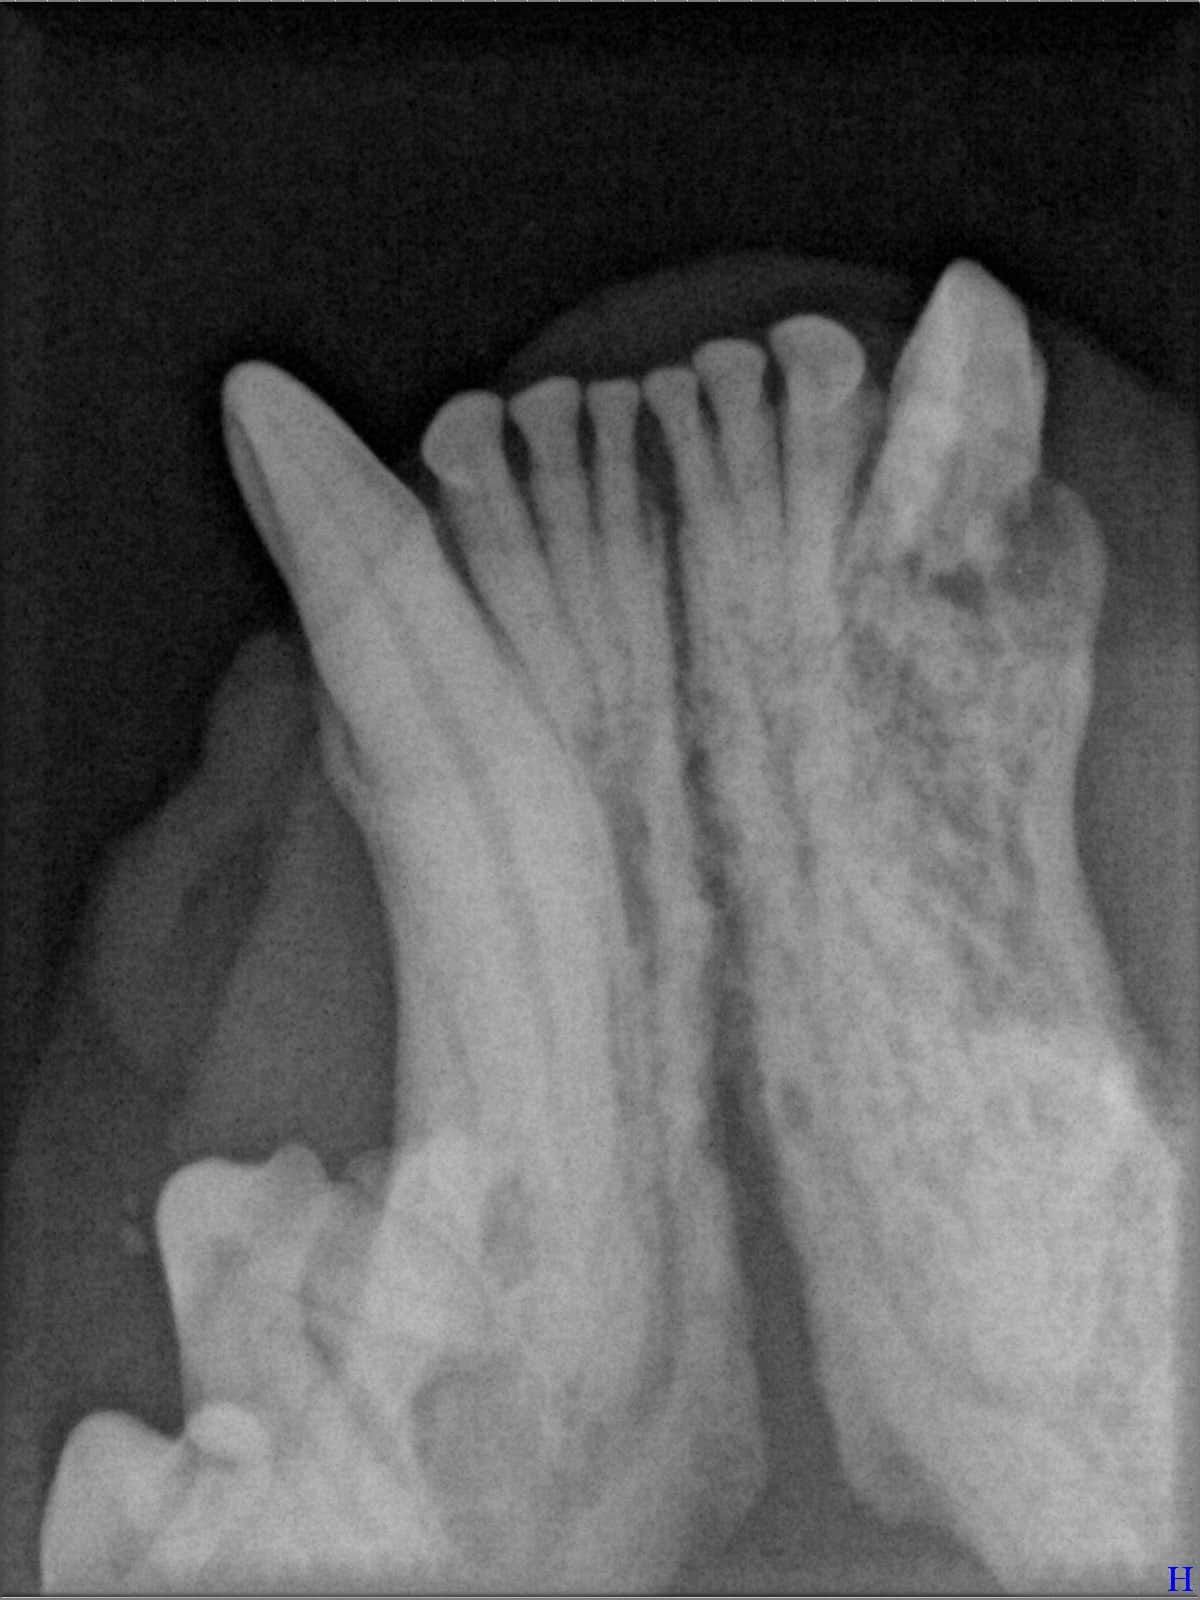

Ein entscheidender Baustein der FORL-Diagnostik ist das dentale Röntgen. Viele Läsionen sind von außen nicht sichtbar und lassen sich ausschließlich mithilfe moderner Röntgentechnik erkennen. In der Hamburger Praxis kommt digitales Dentalröntgen zum Einsatz, das detailreiche Aufnahmen bei geringer Strahlenbelastung ermöglicht. So kann FORL bereits in frühen Stadien diagnostiziert werden.

Das sehen Sie von außen – so sieht es auf den Röntgenbildern aus.

FORL Katze Röntgenbild

Röntgenbilder